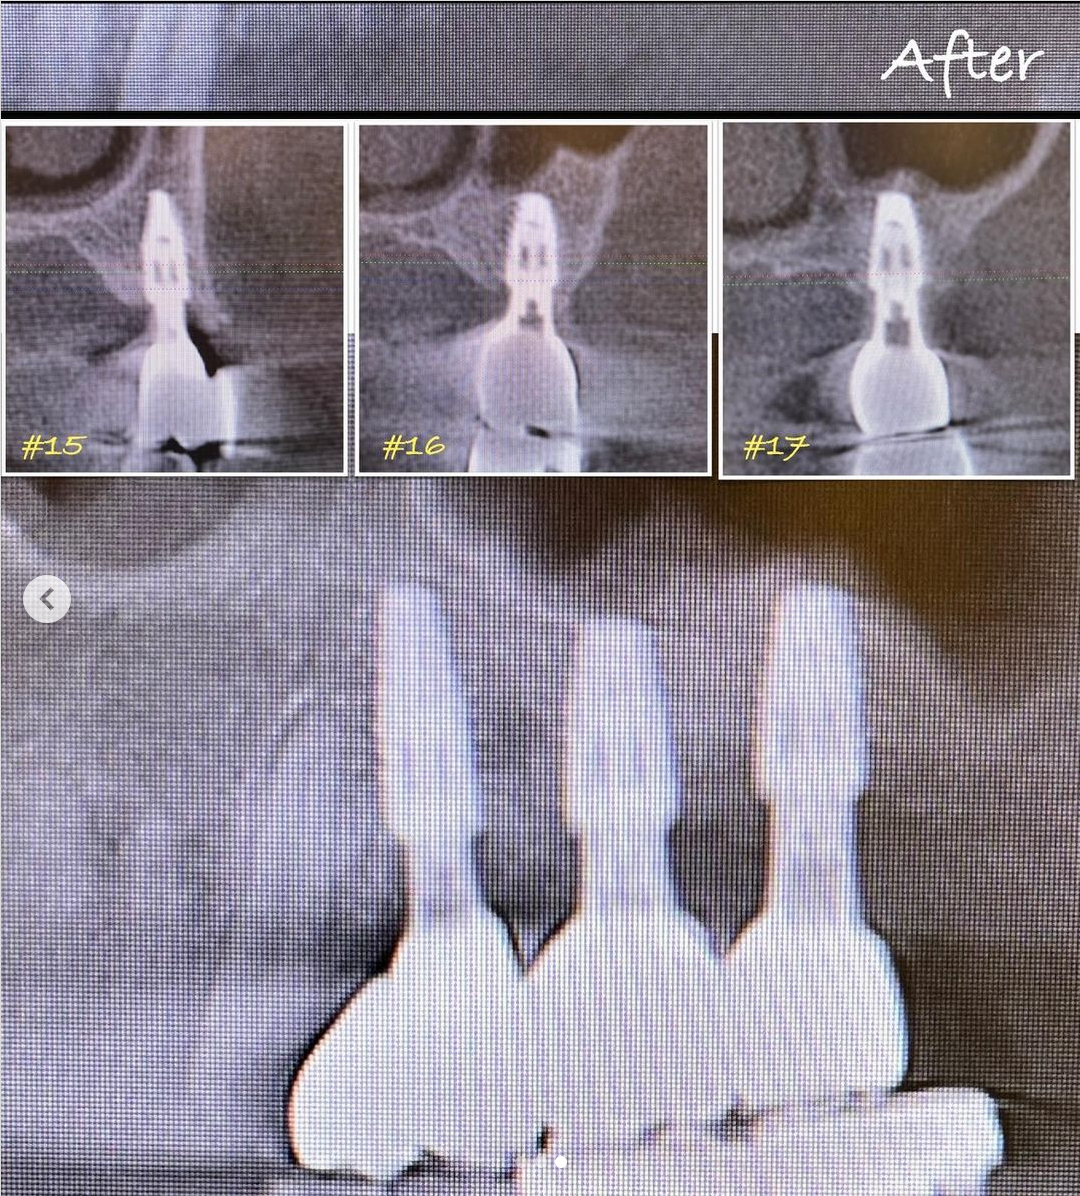

症例紹介8:臼歯インプラント治療《60代女性》

ーーーーーーーーーーーーーーーーーーー

《治療名》

臼歯インプラント治療

《患者情報》

60代 女性

《執刀医(担当医)》

Dr.松本

《治療内容》

奥歯の骨がなく他院で治療を断られた患者さんです。

サイナスリフトという骨造成手術をおこなったあと、インプラントを入れました。

インプラントもサージカルガイドを使用することにより安全に手術を行うことができます。

《治療期間》

1年

《費用(税込)》

¥465,000(税込) / 本

《リスク》

インプラントが感染し、抜ける場合があります。

しかし、安全に配慮ししっかりとした環境で手術を行うことによってそれを限りなくゼロに近づくことができます。